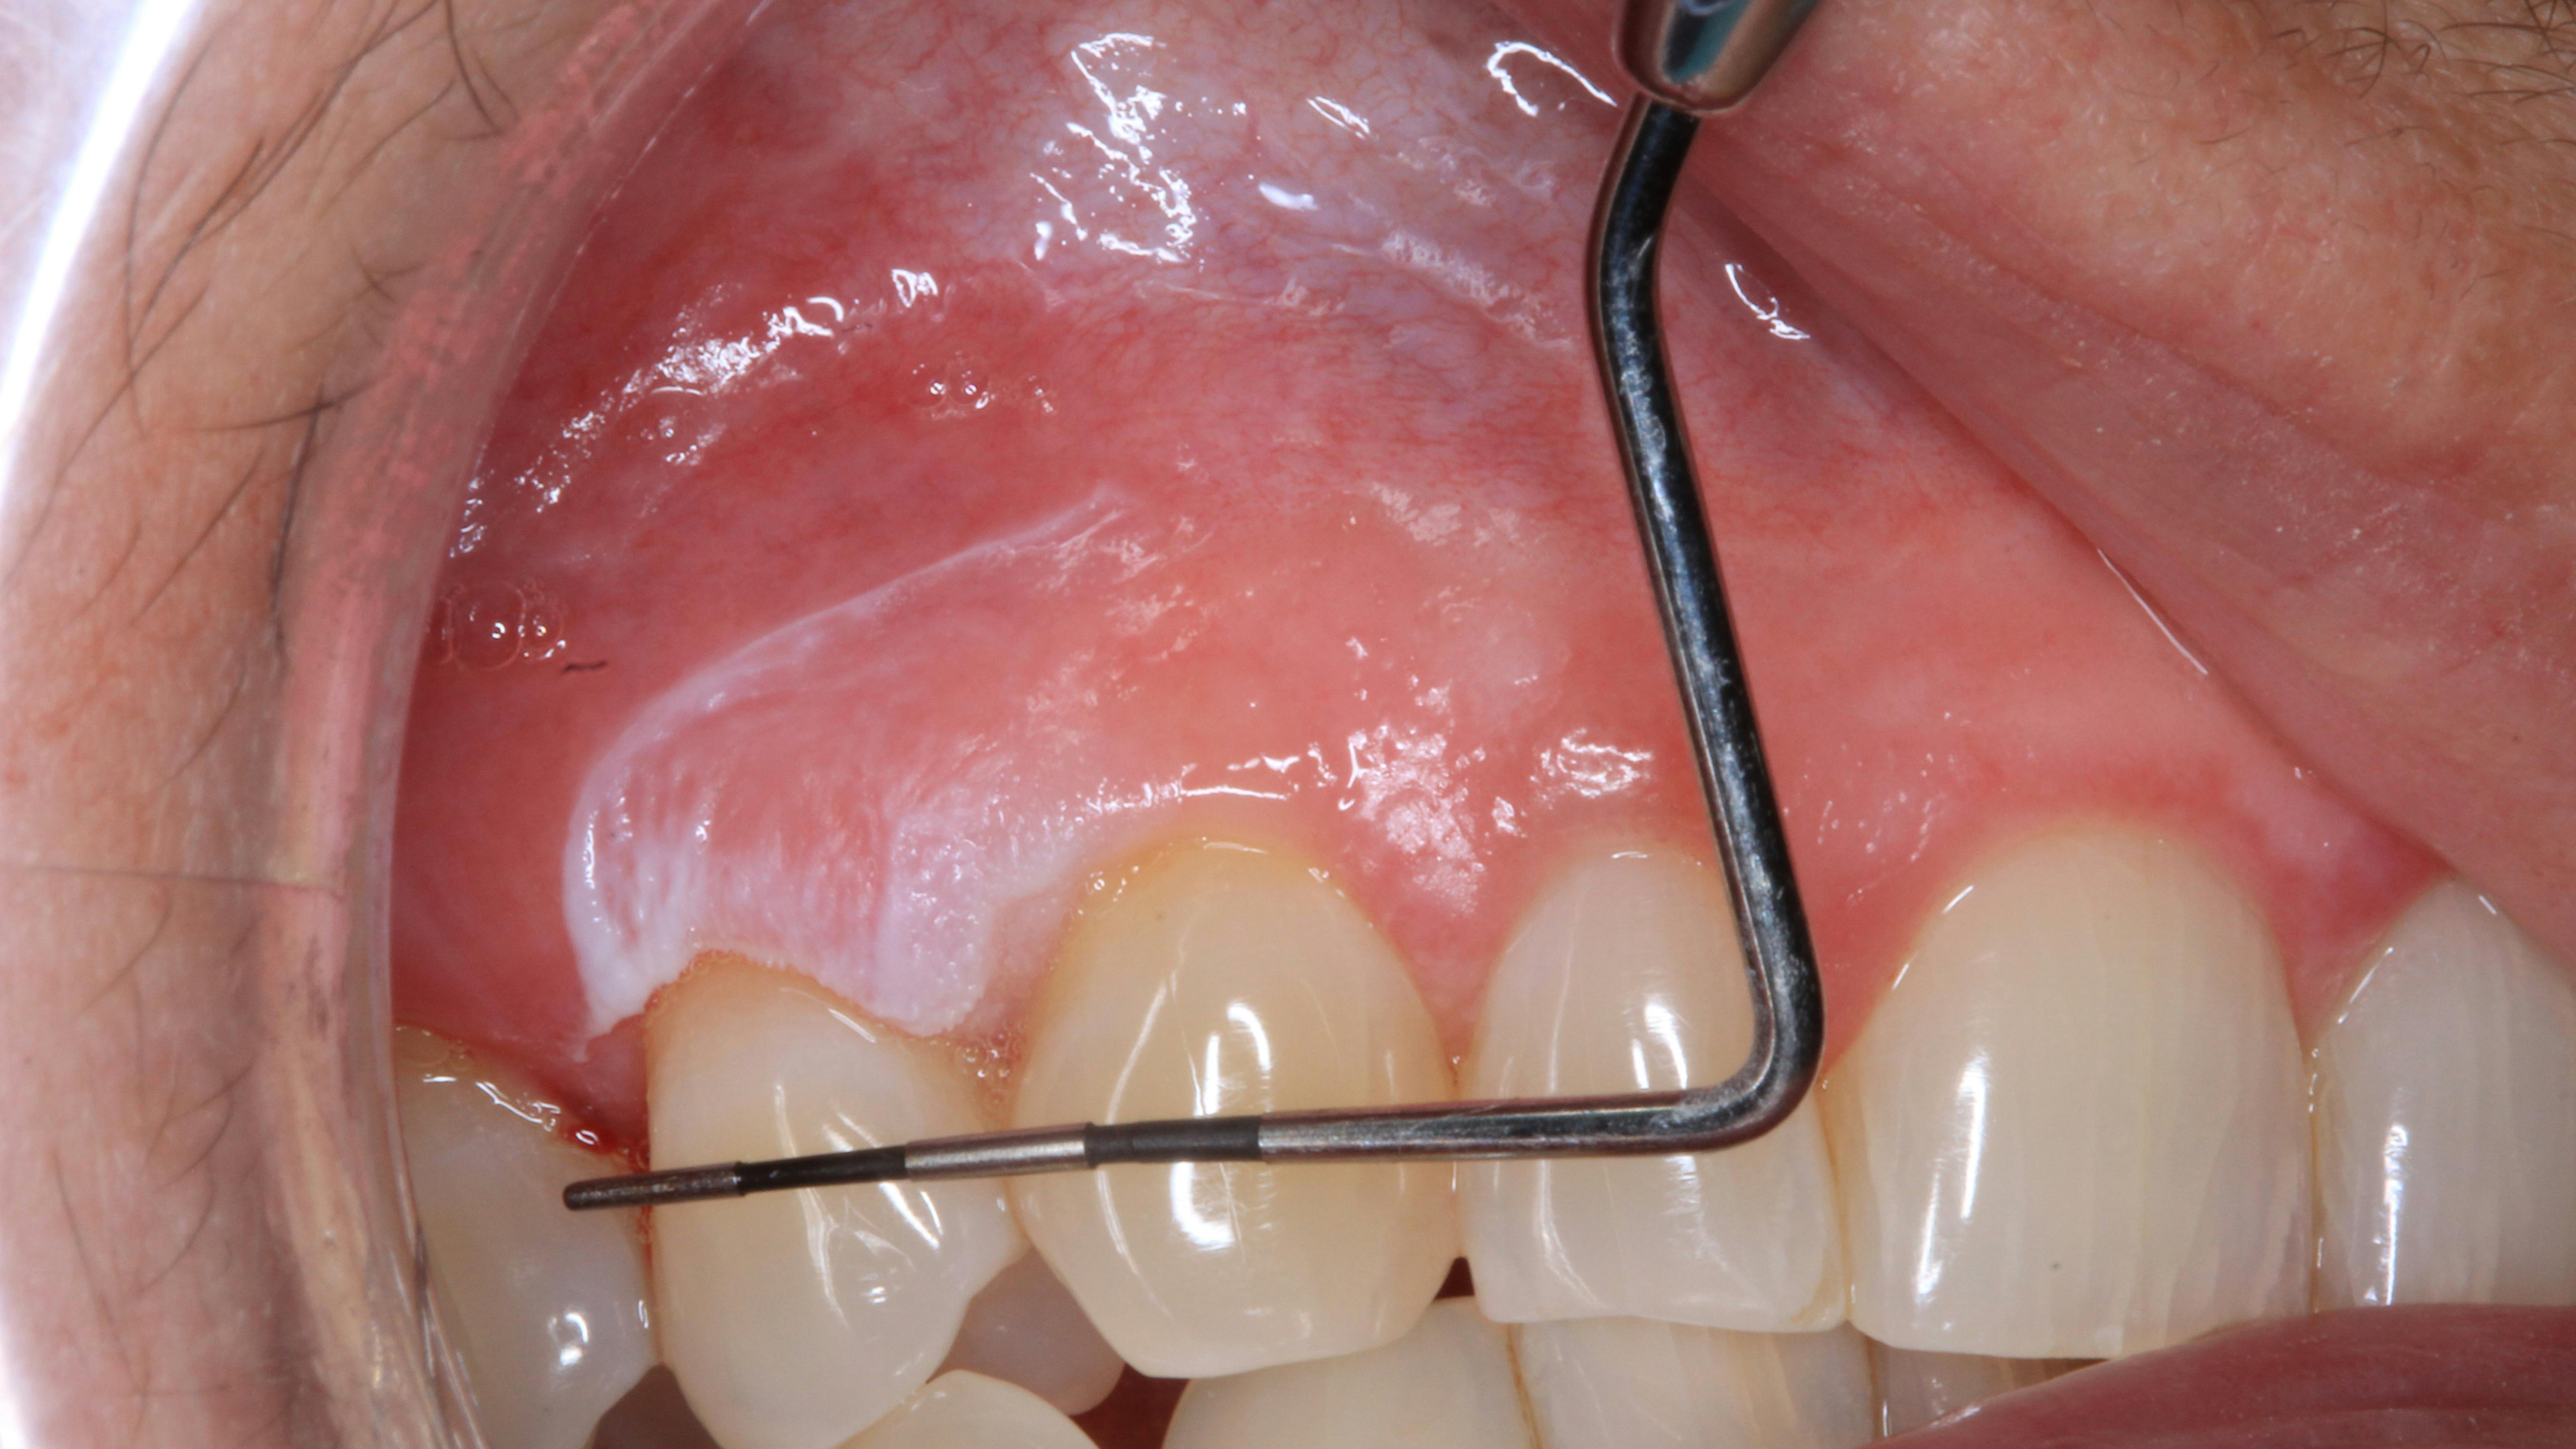

Figure 2: 6 mm x 9 mm irregular-shaped lesion appears white